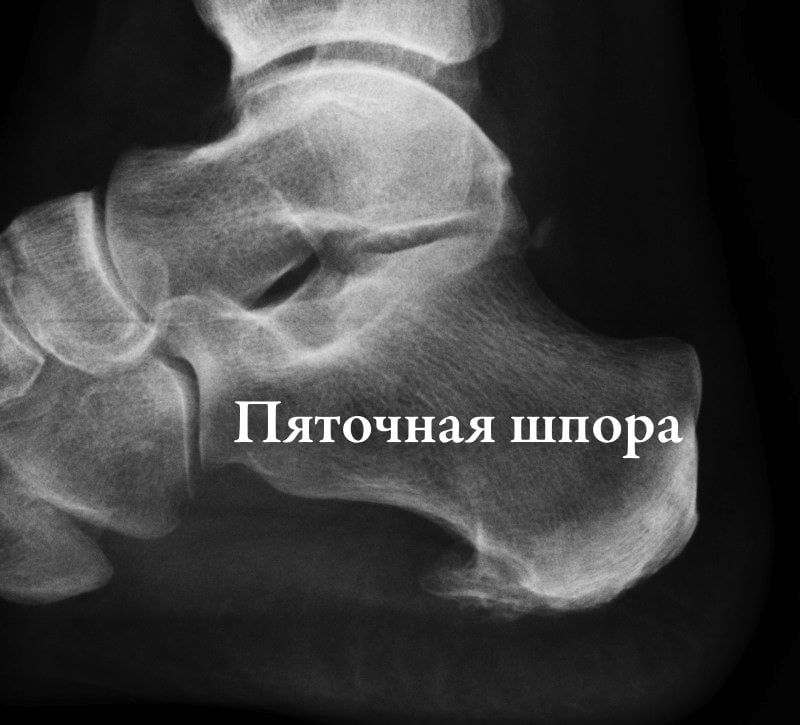

Рентген нароста.

Среди всех заболеваний мышечно-костной системы на долю пяточной шпоры приходится около 10% случаев. Ей особенно подвержены женщины старше 40 лет. Клинически пяточная шпора проявляется острой болью в начале движения, ослабевающей через некоторое время. К ее лечению практикуется комплексный подход — применяются местные и системные препараты, физиопроцедуры, массаж. При неэффективности консервативной терапии пациентам рекомендовано хирургическое вмешательство.

- рентгенография стопы. На полученных изображениях хорошо просматриваются костный нарост. Рентгенография также применяется для исключения патологий со схожей симптоматикой, например, остеоартроза или перелома пяточной кости;